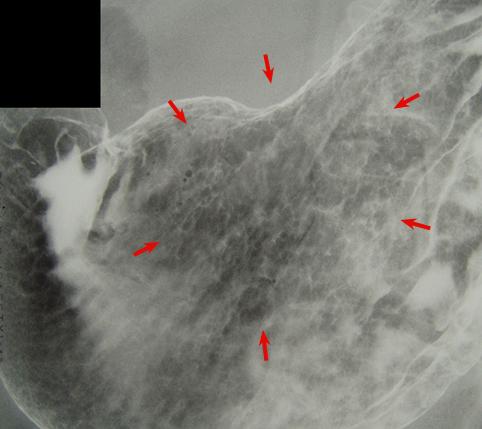

Criteria of Hist.ClassificationMalignant epithelial tumor/Adenocarcinoma

LocationStomach/Angle

Technique, MethodX-ray

Macroscopic TypesType 0/IIc (IIc) Superficial depressed type

Size30 - 34

Depth of Tumor Invasionmucosa